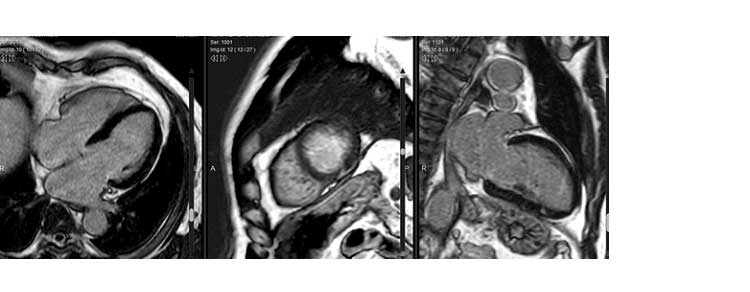

Lo studio permette di studiare la cinetica cardiaca e i difetti del muscolo miocardio dopo un infarto o per lo studio di patologie congenite. Può essere eseguito con e senza mezzo di contrasto in base alla patologia da analizzare.